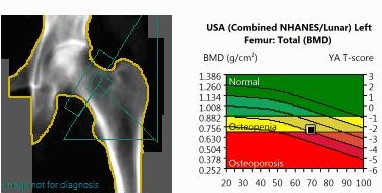

Bone Densitometry (BMD)

BMD